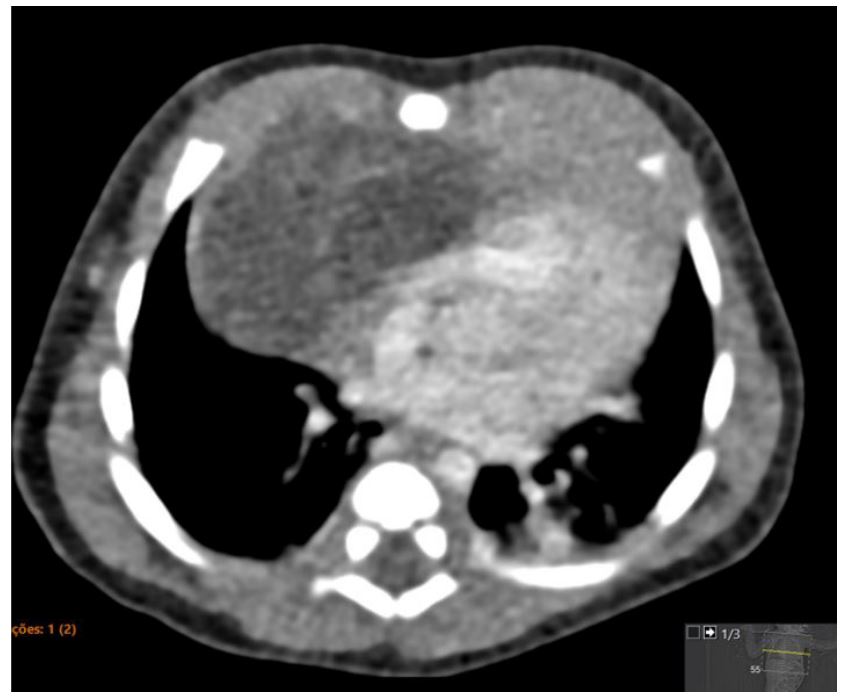

On day 7, a computed tomography (CT) scan of the chest showed a well-defined tumor measuring 60 x 54 x 32 mm, heterogeneous and with areas of calcification (Figure 4). It was closely associated with the mediastinal vessels and caused a mass effect in the thorax, although no pleural effusion was observed.

Figure 4 Postnatal CT scan showing a hypodense cystic mass with thin septa with contrast enhancement.